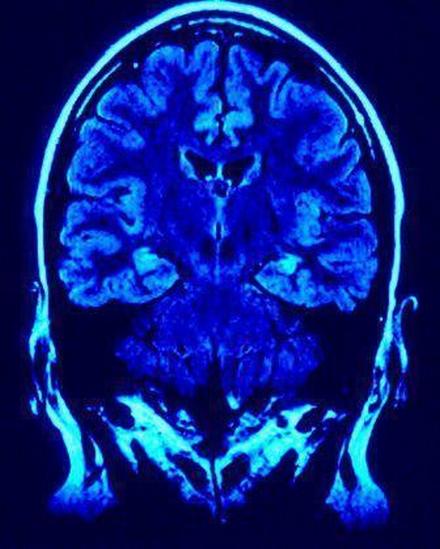

"Injury Compensation Fund - The fund of at least $675 million will be available to pay monetary awards to retired players who present medical evidence of severe cognitive impairment, dementia, Alzheimer's, ALS, or to their families. The precise amount of compensation will be based upon the specific diagnosis, as well as other factors including age, number of seasons played in the NFL, and other relevant medical conditions. These determinations will be made by independent doctors working with settlement administrators appointed by the District Court."

As a result, in order for an injured player or his family to obtain money from this fund, determinations as to the "severity" of the brain injuries will have to be evaluated by "independent doctors working with settlement administrators appointed by the District Court." Of course, this begs the question, what about the players who are only determined to have mild traumatic brain injuries? Where is the line going to be drawn determining the degree of injury for these players?